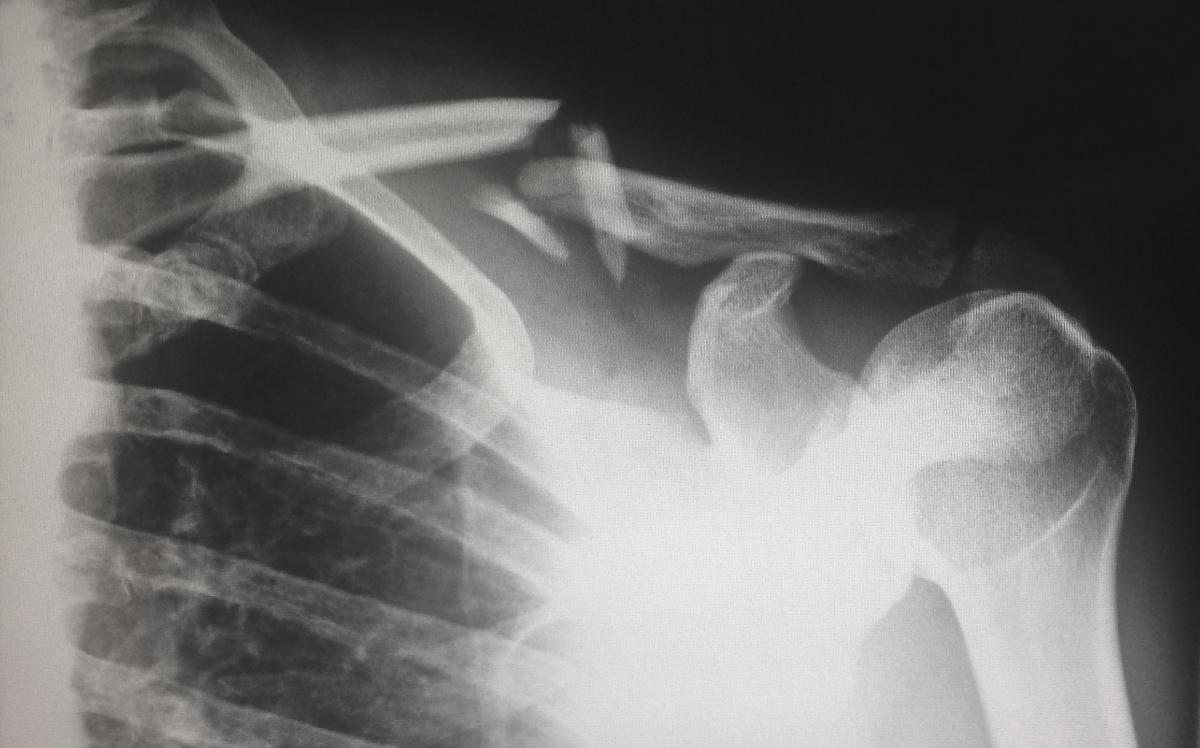

22. A Fortunate Fracture

Had a car crash at 120mph and walked away with a fractured collarbone, pretty lucky I’d say. When the police came and spoke to me they said they saw the car and were expecting to be cutting bodies out of the car. I was a passenger and the driver had a few bruises but that was it.

They also calculated that my friend was less than an inch from injuring his head on a pole sticking out of the back of the truck we hit.